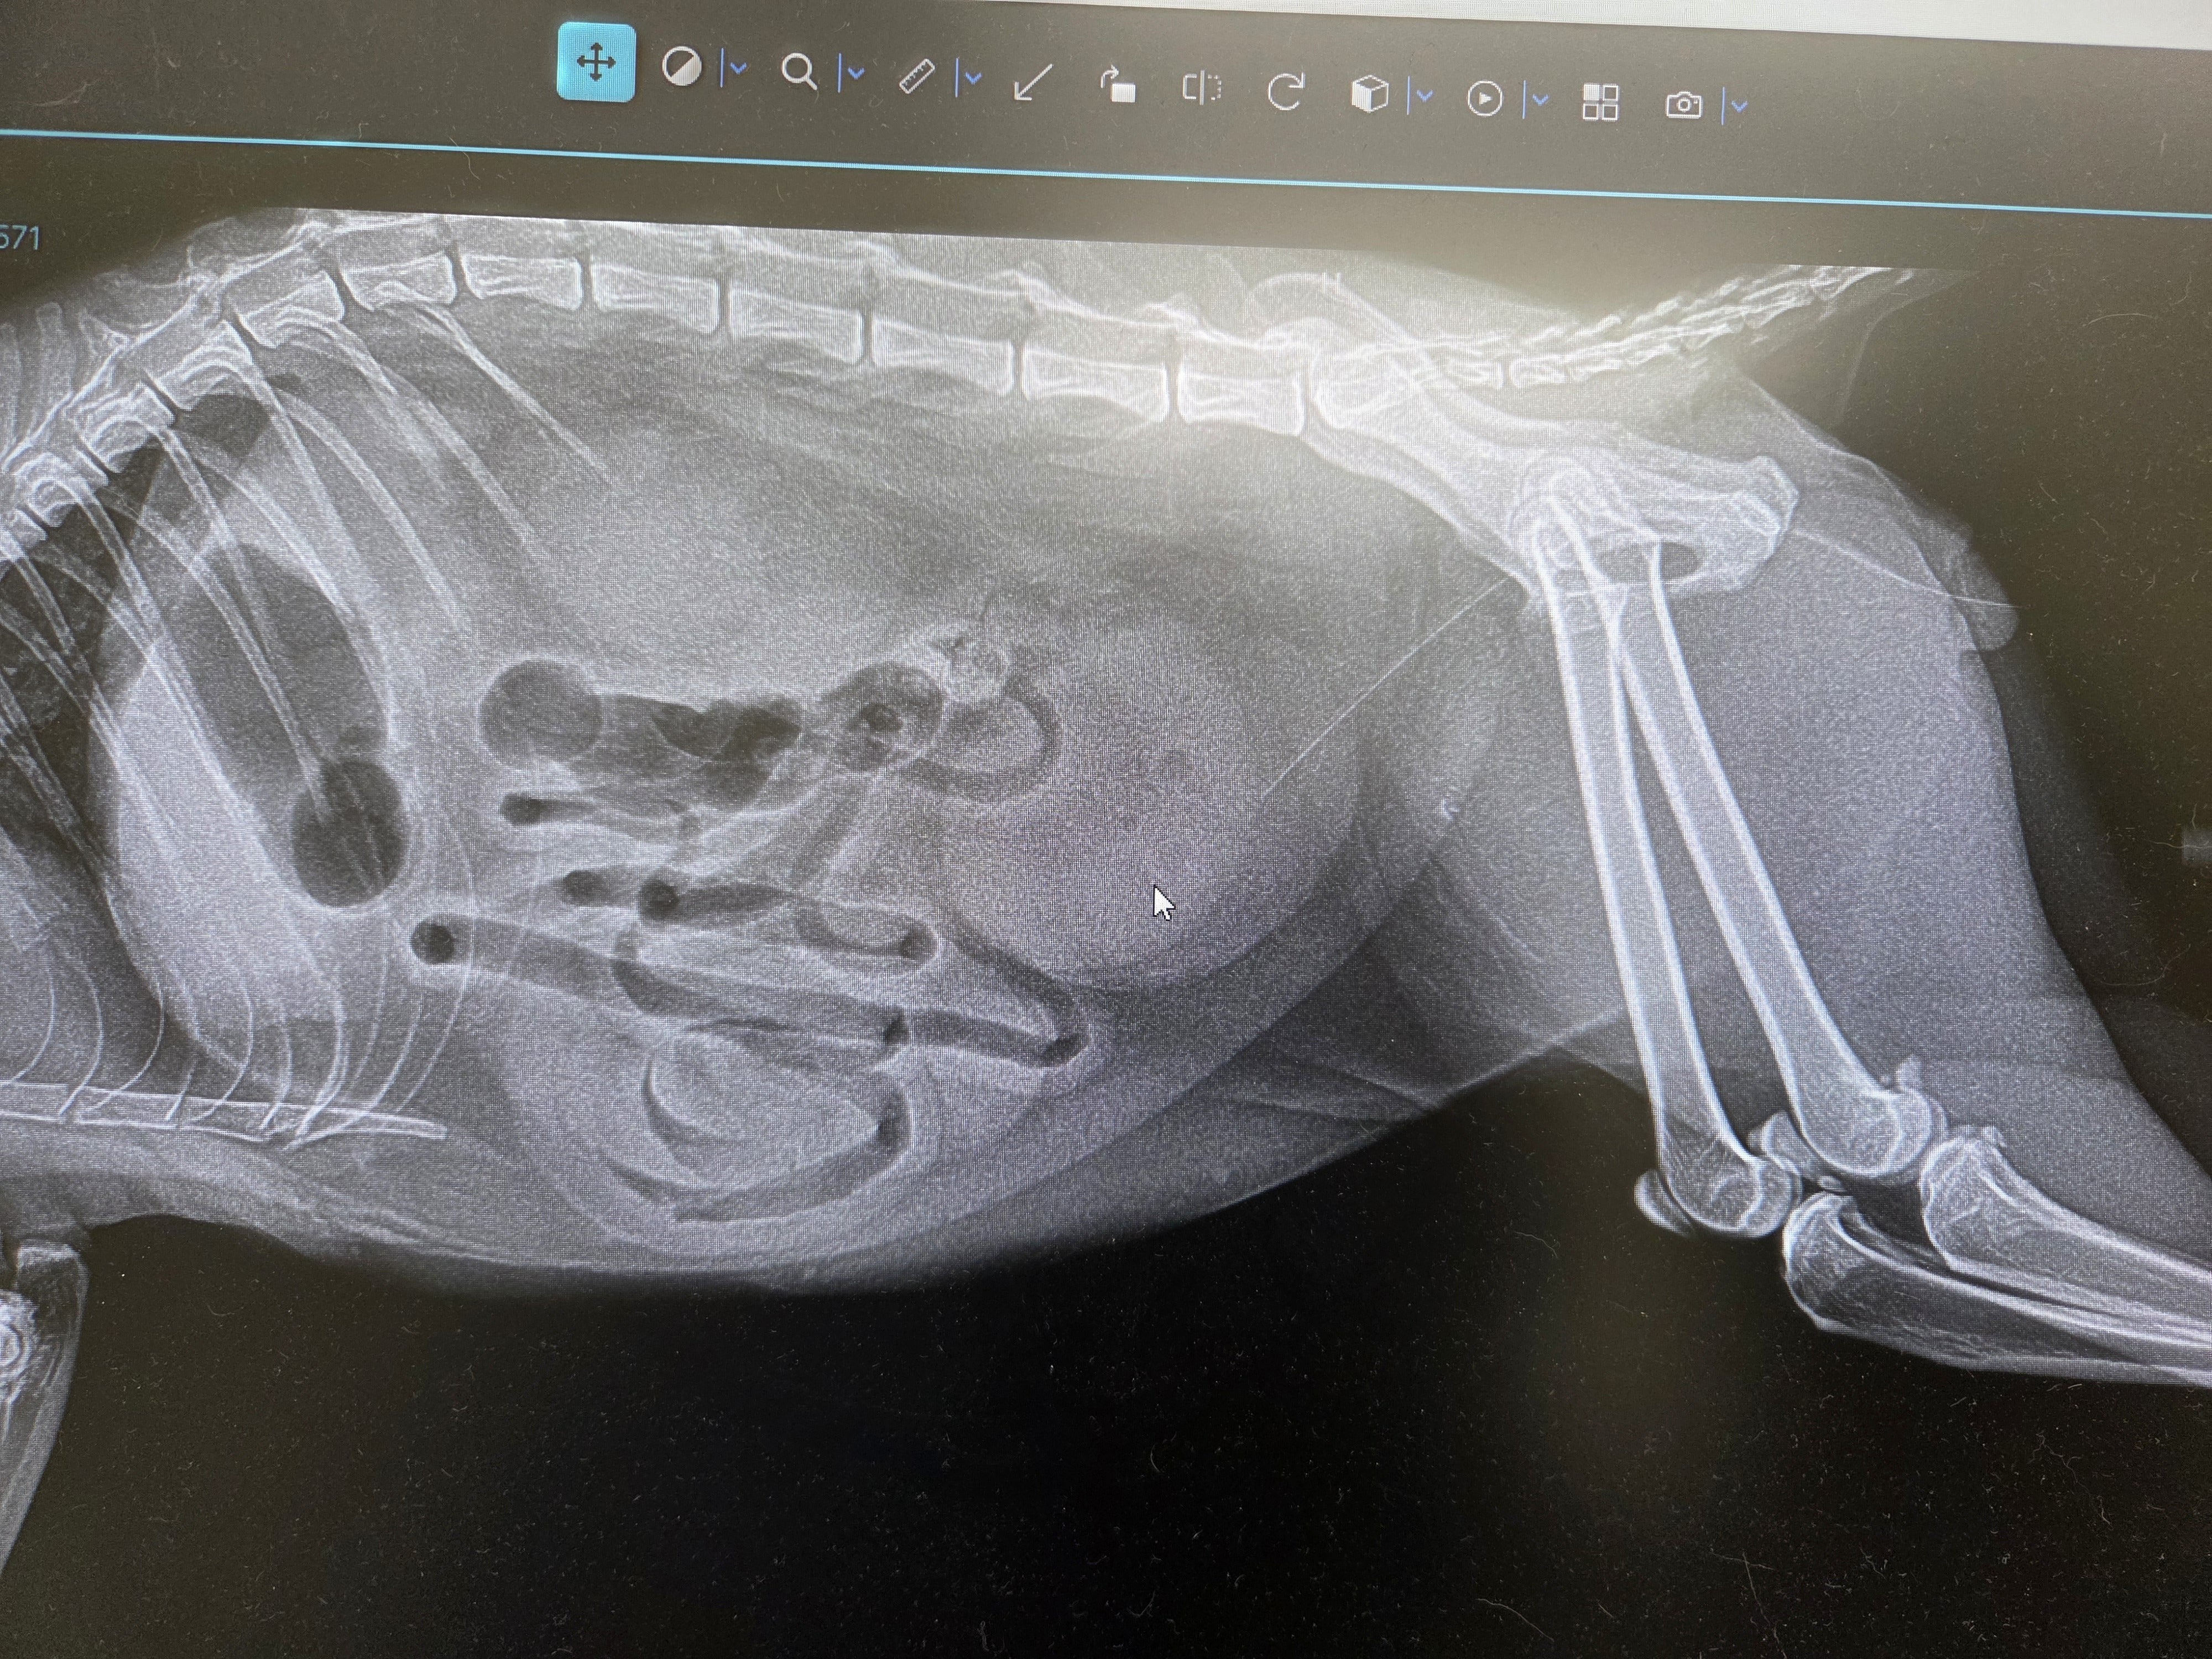

すぐに受診したところ、尿閉によっておしっこが全く出ておらず、腎機能は最悪で、更にカリウム値はいつ心停止してもおかしくない状態でした。

膀胱にカテーテルを入れて、出ないおしっこが出るようにしています。血尿が出続けています。声をかけてもグッタリしていて……でも、わずかに耳を動かしてくれました。